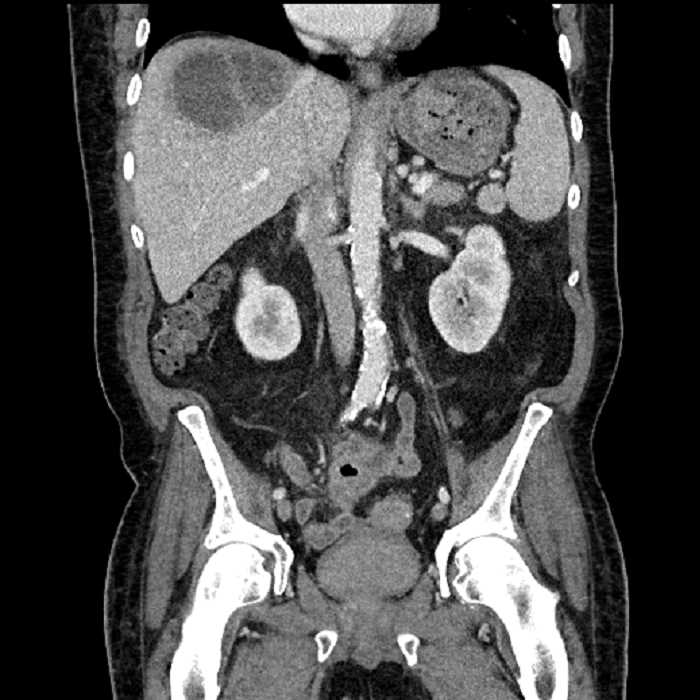

Age: 63

Sex: Male

Indication: Abdominal pain

• Large fluid density structure in hepatic segments 7 and 8 measuring 10 x 7 x 7 cm with internal septation and circumferential ill-defined low density compatible with edema

• Peripherally enhancing subcapsular collections along the anterior margin of the left hepatic lobe measuring 3 x 1 cm and 2 x 1 cm

• Clearly marginated fluid density structure in segment 7 and several other scattered tiny hypodensities, which likely represent cysts

• Hepatic abscess

Acute sigmoid diverticulitis complicated by a small contained perforation and a large abscess in the right hepatic lobe. Additional small subcapsular abscesses along the anterior margin of the left hepatic lobe.

• The classic CT imaging appearance is a double target sign with internal low density surrounded by an internal enhancing rim (capsule) and a low density external rim (edema)

Hepatic abscess showing the double target sign with low density internally surrounded by a thin inner enhancing rim (red arrow) and ill-defined outer low density rim (yellow arrow). Blue arrow indicates an internal septation. Red arrows: additional smaller subcapsular abscesses. Red arrow: focal contained perforation associated with diverticulitis.